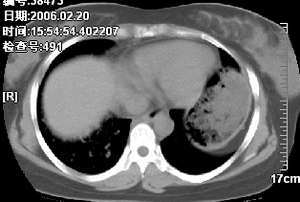

右肺下叶炎性病变,治疗后复查。

已经手术结果为淋巴瘤

非常好的病例,中青年患者应该想到淋巴瘤

纵隔内淋巴结肿大不是非常明显。但肺部征象明显。还是第一次见到。学习了!!!!!

补充病例结果是:肺间变大t细胞淋巴瘤. 非霍奇金淋巴瘤(间变大t细胞性)iv期bipi 2分

右肺中下叶切除